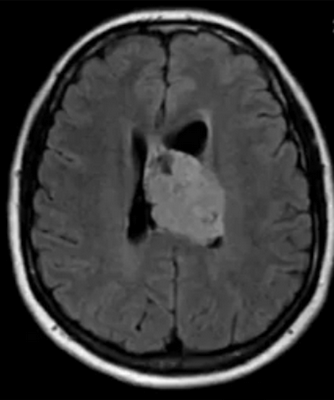

Эпендимома при МР-сканировании головного мозга